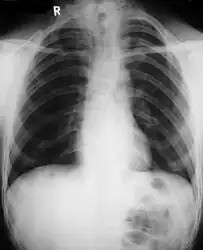

Cleidocranial dysostosis (CCD), also called cleidocranial dysplasia, is a birth defect that mostly affects the bones and teeth.[1] The collarbones are typically either poorly developed or absent, which allows the shoulders to be brought close together.[1] The front of the skull often does not close until later, and those affected are often shorter than average.[1] Other symptoms may include a prominent forehead, wide set eyes, abnormal teeth, and a flat nose.[1] Symptoms vary among people; however, intelligence is typically unaffected.[1]

Cleidocranial dysostosis is a general skeletal condition[8] so named from the collarbone (cleido-) and cranium deformities which people with it often have.

• Clavicles (collarbones) can be partly missing leaving only the medial part of the bone. In 10% of cases, they are completely missing.[10] If the collarbones are completely missing or reduced to small vestiges, this allows hypermobility of the shoulders including ability to touch the shoulders together in front of the chest.[11] The defect is bilateral 80% of the time.[12] Partial collarbones may cause nerve damage symptoms and therefore have to be removed by surgery.

Different features of the dysostosis are significant. Radiological imaging helps confirm the diagnosis. During gestation (pregnancy), clavicular size can be calculated using available nomograms. Wormian bones can sometimes be observed in the skull.[19]